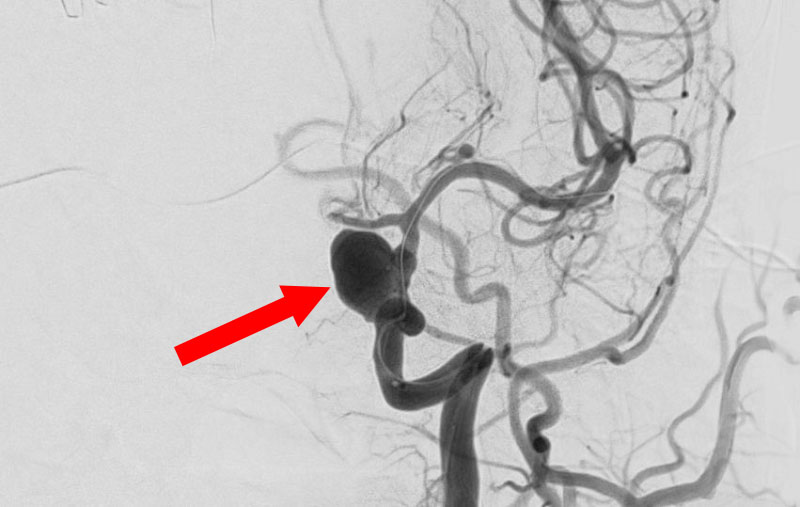

No.1594 手術前